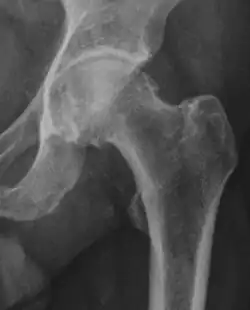

X-ray

Projectional radiography ("X-ray") is often considered first line for FAI.[10] Anterior-posterior pelvis and a lateral image of the hip in question should be attained.[10] A 45-degree Dunn view is also recommended.[10][19]